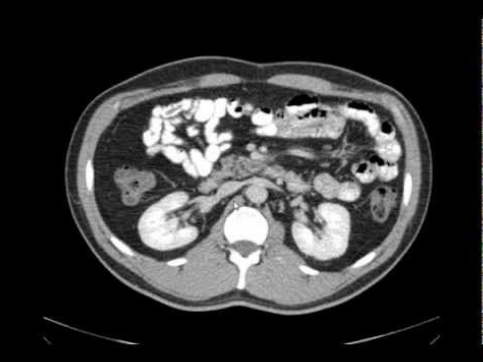

Visualização anatômica do abdômen em tomografia computadorizada (Fonte: Radiology Key)